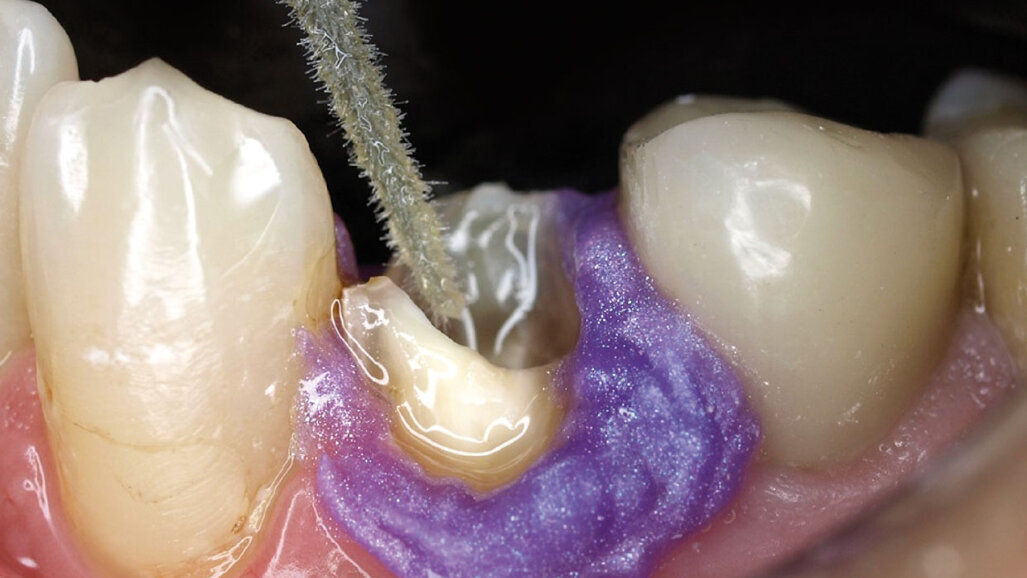

Obr. 7: Stanovení délky – Obr. 8: Gingivální bariéra

Během dostavby zub izolujeme kofferdamem nebo gingivální bariérou (obr. 8). Kořenovou výplň odstraníme vrtákem až do stanovené hloubky, čímž kanálek zároveň preparujeme na správný průměr (obr. 9). Kontrolu přesnosti dosazení čepu provedeme prostřednictvím rtg snímku. Čep je jasně rentgenkontrastní (obr. 10). Poté jej diamantem zkrátíme na požadovanou délku. Na obr. 11 je patrný kanálek po opracování a před aplikací bondu.